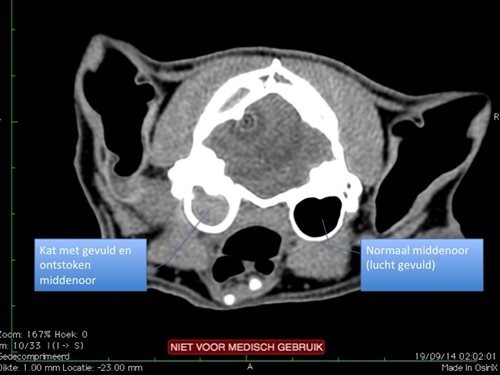

- De doorsnedes laten toe om dingen te zien die anders niet zichtbaar zouden zijn.